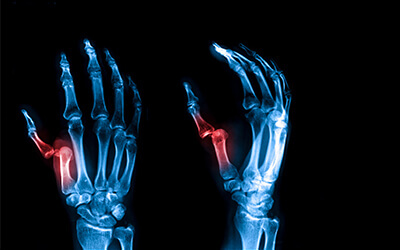

FINGER THUMB SPRAIN

FINGER & THUMB SPRAIN

A finger or thumb sprain occurs when ligaments are stretched or torn, usually from a sudden twist or impact, causing pain, swelling, and limited movement.